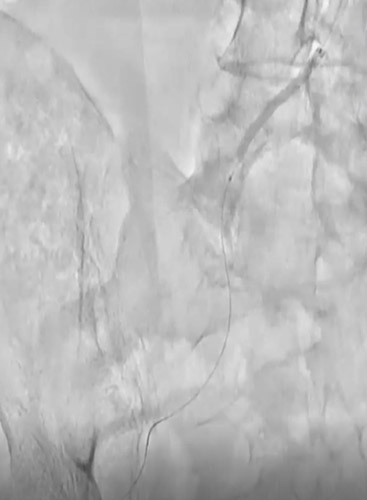

CIAにR2P Misago 9-40mmを留置。ステントproximalはCIA入口部ジャストに合わせたが、R2P Misagoはリリース時に位置ずれしにくく狙った位置に留置できた(図7)。

その後、Senri 6-40mmでポスト拡張。動脈瘤部も造影剤の染み出しもなく終了した(図8)。